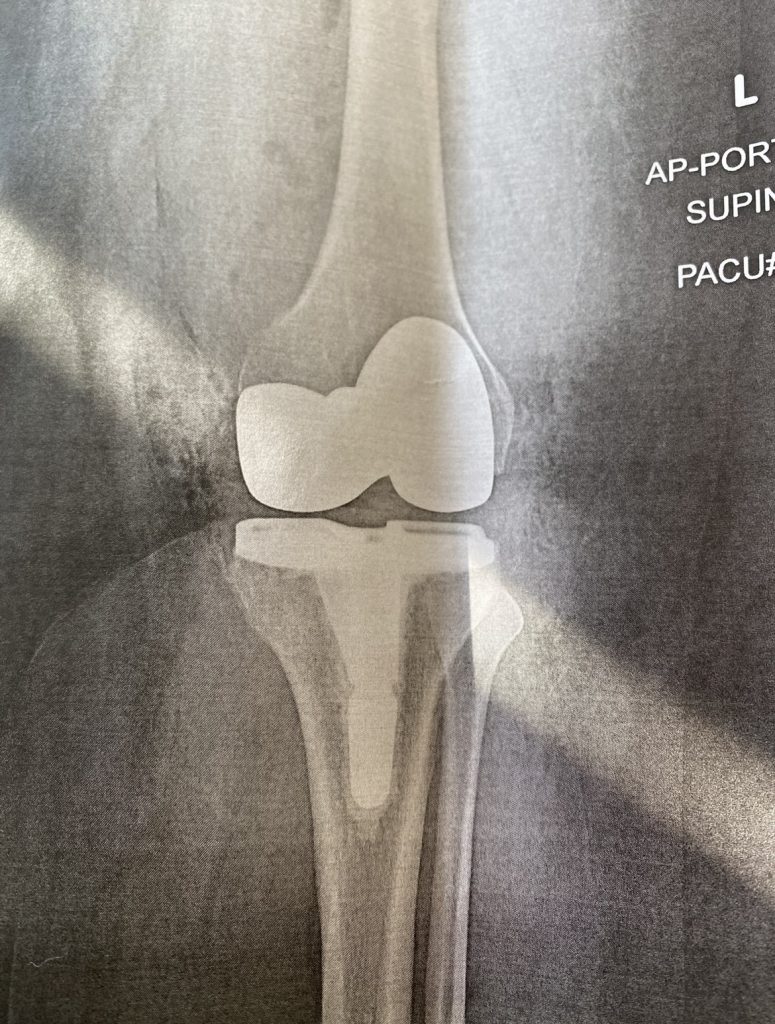

My left knee replacement surgery was FINALLY completed on 12/13/2021 at the main hospital and after 4 months of physical therapy my knee is doing GREAT. I have since returned to work. I can't thank Dr. Gausden and my physical therapist Asma enough! They're so amazing. I was scared at first to have my knee replaced but now I can't wait to replace my right knee and really get moving again. Thank you all so much.

Dr. Gausden was amazing. The first time I stepped into her office was in October 2020. I loved her bedside manner and the way she took the time to explain my osteoarthritis diagnosis to me. You see, I visited Dr. Gausden after being advised to get a second opinion regarding my excruciating knee pain. I left her office knowing she would take great care of me. I decided to let Dr. Gausden perform my left knee replacement in December 2021. My left knee is doing GREAT! Fast forward to October 2023 and I now have a new right knee. If you are looking for a great orthopedic surgeon, look no further. Seek Dr. Gausden’s care. You will not be disappointed!